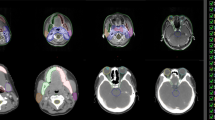

CT images showing different OAR contours Reference contours according to the ICG (lilac) vs delineations from the different RO. a brainstem (sagittal plane): difference in cranial and caudal borders; b oral cavity, spinal cord and PG (axial plane): Inclusion of buccal mucosa (green contour) and teeth (orange and pink contours) by some RO. Variation in spinal cord and PG contours; c spinal cord (sagittal plane): difference in cranial and caudal borders. ICG international consensus guidelines, PG parotid glands, RO radiation oncologist

The brainstem was delineated in 89% of cases (no difference between the two RO groups). Most RO in this study started delineation in the most cranial slice where the brainstem was visible. The caudal border differed with a few slices between RO but was mostly according to the guidelines (Table 2, Fig. 3a). The circumferential contour on the axial plane showed little variation (Additional file 6: Fig. 4a). On visual inspection of the contours, there was no clear difference between the two groups of RO.

Spinal cord

The spinal cord was delineated in 82% of cases (62% with ICG vs 97% without) and the spinal canal in the other cases (two RO who both used the ICG and once by a RO in the other group) (Fig. 3b). Besides this, the largest differences were seen in the cranial border (depending on the caudal border of the brainstem) and the caudal border (Fig. 3c). Some RO delineated the spinal cord all the way to the most caudal slice of the CT scan, others stopped several slices higher. Three RO stopped a few slices cranial to T3 in one patient each.

There are several reasons that could explain the contour variation between RO and the reference contour in the present study. A reason that has already been mentioned, is that different guidelines are used, either because the ICG [18] were not known to exist, or because other guidelines were used. The effect of using the ICG could clearly be seen on several OARs, namely the cochleas, glottic area, PCMs and supraglottic larynx, which were delineated more often and with better agreement. Figures 1 and 2 support this hypothesis because MSD is significantly smaller for the RO using the ICG compared to the other group (p = 0.008). However, even when the ICG are used, there was still IOV compared to the reference contours. A first possible reason is that the edges of the OARs may be unclear/blurry on CT (PCMs, anterior and medial borders of PGs), needing interpretation by the delineating RO, which can result in IOV. Secondly, different CT windowing can also have an impact on OAR visualisation, resulting in different volumes. Thirdly, the guidelines might be misunderstood or misinterpreted. For example the supraglottic larynx which should start cranially at the tip of the epiglottis was delineated by one RO including the air surrounding the tip (Additional file 6: Fig. 4n). The inclusion of air has a large impact on the volume delineated, which is also often seen in case of the oral cavity. Another misinterpretation occurs at the cranial and caudal borders, which often differed a few slices. For example at the caudal border of the brainstem, because the “tip of the dens of C2” can be prone to misinterpretation (Fig. 3a). Also the spinal cord showed variation in the caudal border because some RO delineated it all the way to the most caudal slice of the CT, and others stopped more cranially. Two RO who used the ICG delineated the spinal canal instead of the spinal cord so these were excluded from the analysis which resulted in less delineations (Table 1) and less agreement (Fig. 2). Not only the delineated volumes differed, but also whether the OAR was delineated or not varied significantly. The mandible, brainstem, spinal cord, salivary glands and oral cavity were consistently delineated in all patients, irrespective of which RO delineated them. But several OARs seem less well-known, especially to RO who did not use the ICG. This resulted in less than half of them to delineate the cochleas, glottic area, PCMs and supraglottic larynx. Even the RO using the ICG did not always delineate the OARs described in the guidelines, even though they did delineate them more often (Table 1). A reason for this could be that the RO may have deemed delineation of the OAR unnecessary for treatment planning because the tumour was situated far away or too close to spare the OAR anyway.